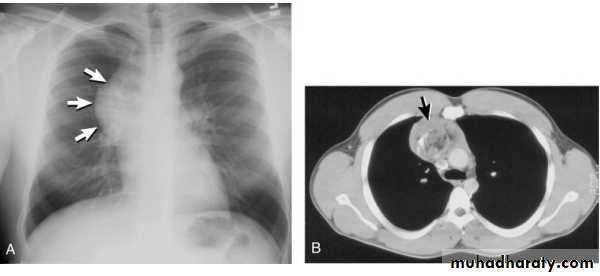

Posteroanterior (A) and lateral (B) chest radiographs demonstrate the typical meniscoid appearance (arrows) in a patient with a left pleural effusionHydropneumothorax.